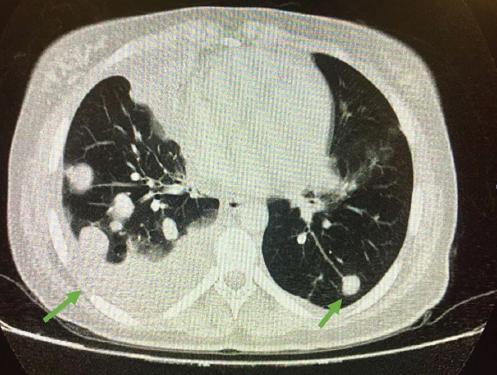

La analítica de sangre muestra una hemoglobina de 9.5 g/dl, b-hCG de 267,789 mUI/ml y hormonas tiroideas elevadas con disminución de la hormona estimulante del tiroides; el resto de los parámetros dentro de la normalidad. La radiografía de tórax se informa con abundantes infiltrados compatibles con metástasis más derrame pulmonar de predominio derecho (Fig. 1). Ante los hallazgos se solicita tomografía computarizada, en la que se objetivan abundantes nódulos en ambos pulmones con componente necrótico (Fig. 2) y placenta posterior con captación heterogénea y crecimientos nodulares/mamelonados (Fig. 3), todo ello compatible con metástasis de coriocarcinoma a confirmar por anatomía patológica.

Figura 2 Tomografía computarizada pulmonar que muestra múltiples lesiones sospechosas de metástasis, la mayoría rodeadas de halo en «vidrio deslustrado» y de captación heterogénea, probablemente necróticas, con atelectasia en el lóbulo medio derecho.